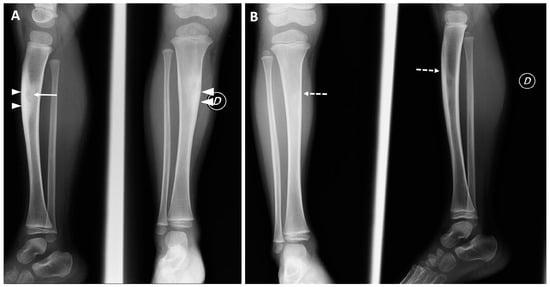

| 35 | 42 | Continuous pain worsened at night | Tibia diaphysis, cortical-periosteal | 12 mm | 15 mm | Yes | Yes | Osteoid osteoma | 4 months after treatment: asymptomatic | 7 years after treatment: asymptomatic |